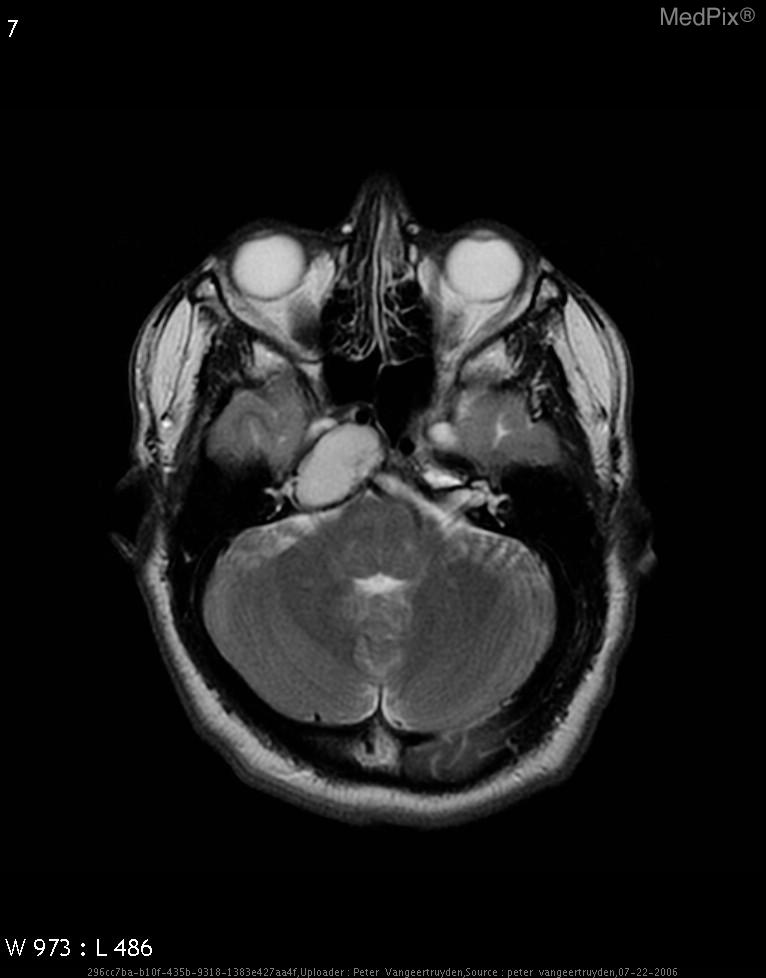

- Axial MRI brain shows a large, well-defined, expansile lesion centered in the petrous apex region on the image-left (patient-right).

- Lesion demonstrates homogeneously high signal intensity on T2-weighted sequence, suggesting fluid or blood product content.

- The mass appears to cause remodeling and expansion of the petrous temporal bone on the image-left (patient-right).

- No definite internal septations or solid enhancing nodules are visible on this T2 image.

- Adjacent structures such as the cerebellum and pons are mildly compressed but not invaded.

- The middle ear and mastoid on the image-left (patient-right) appear partially effaced.

- Optic apparatus and contralateral (image-right, patient-left) structures are normal.

- No diffusion restriction or perilesional edema is observed on this sequence (though confirmation requires DWI).

2) Most likely diagnosis and why:

Cholesterol granuloma of the petrous apex (image-left = patient-right). This diagnosis is favored due to the well-circumscribed expansile lesion in the petrous apex with homogeneous T2 hyperintensity and smooth bony expansion, typical for a cholesterol granuloma containing blood degradation products. No solid component or irregular enhancement pattern suggests a cystic, benign process rather than neoplastic. Context consistency: Consistent — matches the provided context of petrous apex cholesterol granuloma in a 64-year-old female. Confidence: 90%